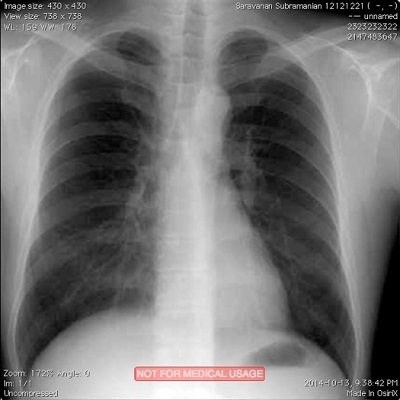

Running the code example above creates a new DICOM file and also lists the attributes of the file to the console. Please note that even though we only supplied 5 attributes during creation of the DICOM file, a lot of other attributes have values that are either generated automatically, or left blank, or with default values. For now, we have created a perfectly valid DICOM image that is encoded correctly for all intents and purposes. Later, we will see how you can add additional attributes to a DICOM object. Screen capture below shows what the new DICOM image looks like when viewing it in OsiriX software running on my Mac workstation.